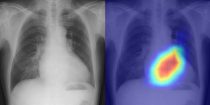

Диагностика болезни сердца Слева: рентгенограмма грудной клетки из тестового набора данных. Справа: наложенная карта заметности, показывающая основания для оценки сердечной функции моделью […]… далее